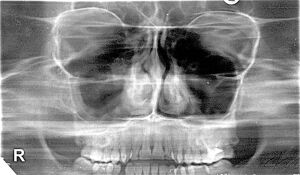

Метод ПАНОРАМНОЙ ЗОНОГРАФИИ (рис.3) является разновидностью ортопантомографии, позволяющей получить изображение более толстого слоя объекта (до 3 см), что повышает информативность метода.

Рис.3. Панорамная зонограмма средней зоны лица